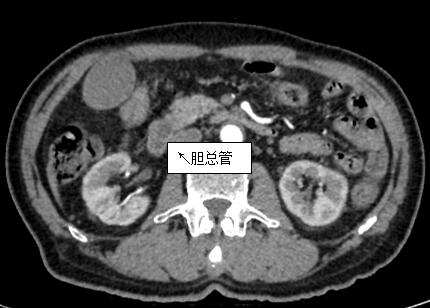

69歲王姓患者,因“發(fā)現(xiàn)無痛性黃疸1月”入院,根據(jù)患者病史,患者診斷傾向于壺腹部腫瘤所致梗阻性黃疸。予以完善腹部CT及上腹部MRI加MRCP均顯示肝內(nèi)外膽管擴(kuò)張,未發(fā)現(xiàn)明顯膽管,胰腺及十二指腸乳頭部腫瘤,且患者CA199正常。以前醫(yī)院未引進(jìn)超聲內(nèi)鏡,這類患者到此就遇到診斷瓶頸。此患者經(jīng)過消化內(nèi)科張丹霞副主任醫(yī)師完善超聲內(nèi)鏡檢查后,可以清楚顯示膽總管下段壁內(nèi)軟組織占位?;颊咄ㄟ^超聲內(nèi)鏡檢查診斷明確,轉(zhuǎn)至肝膽外科行手術(shù)治療。

上腹部CT圖片